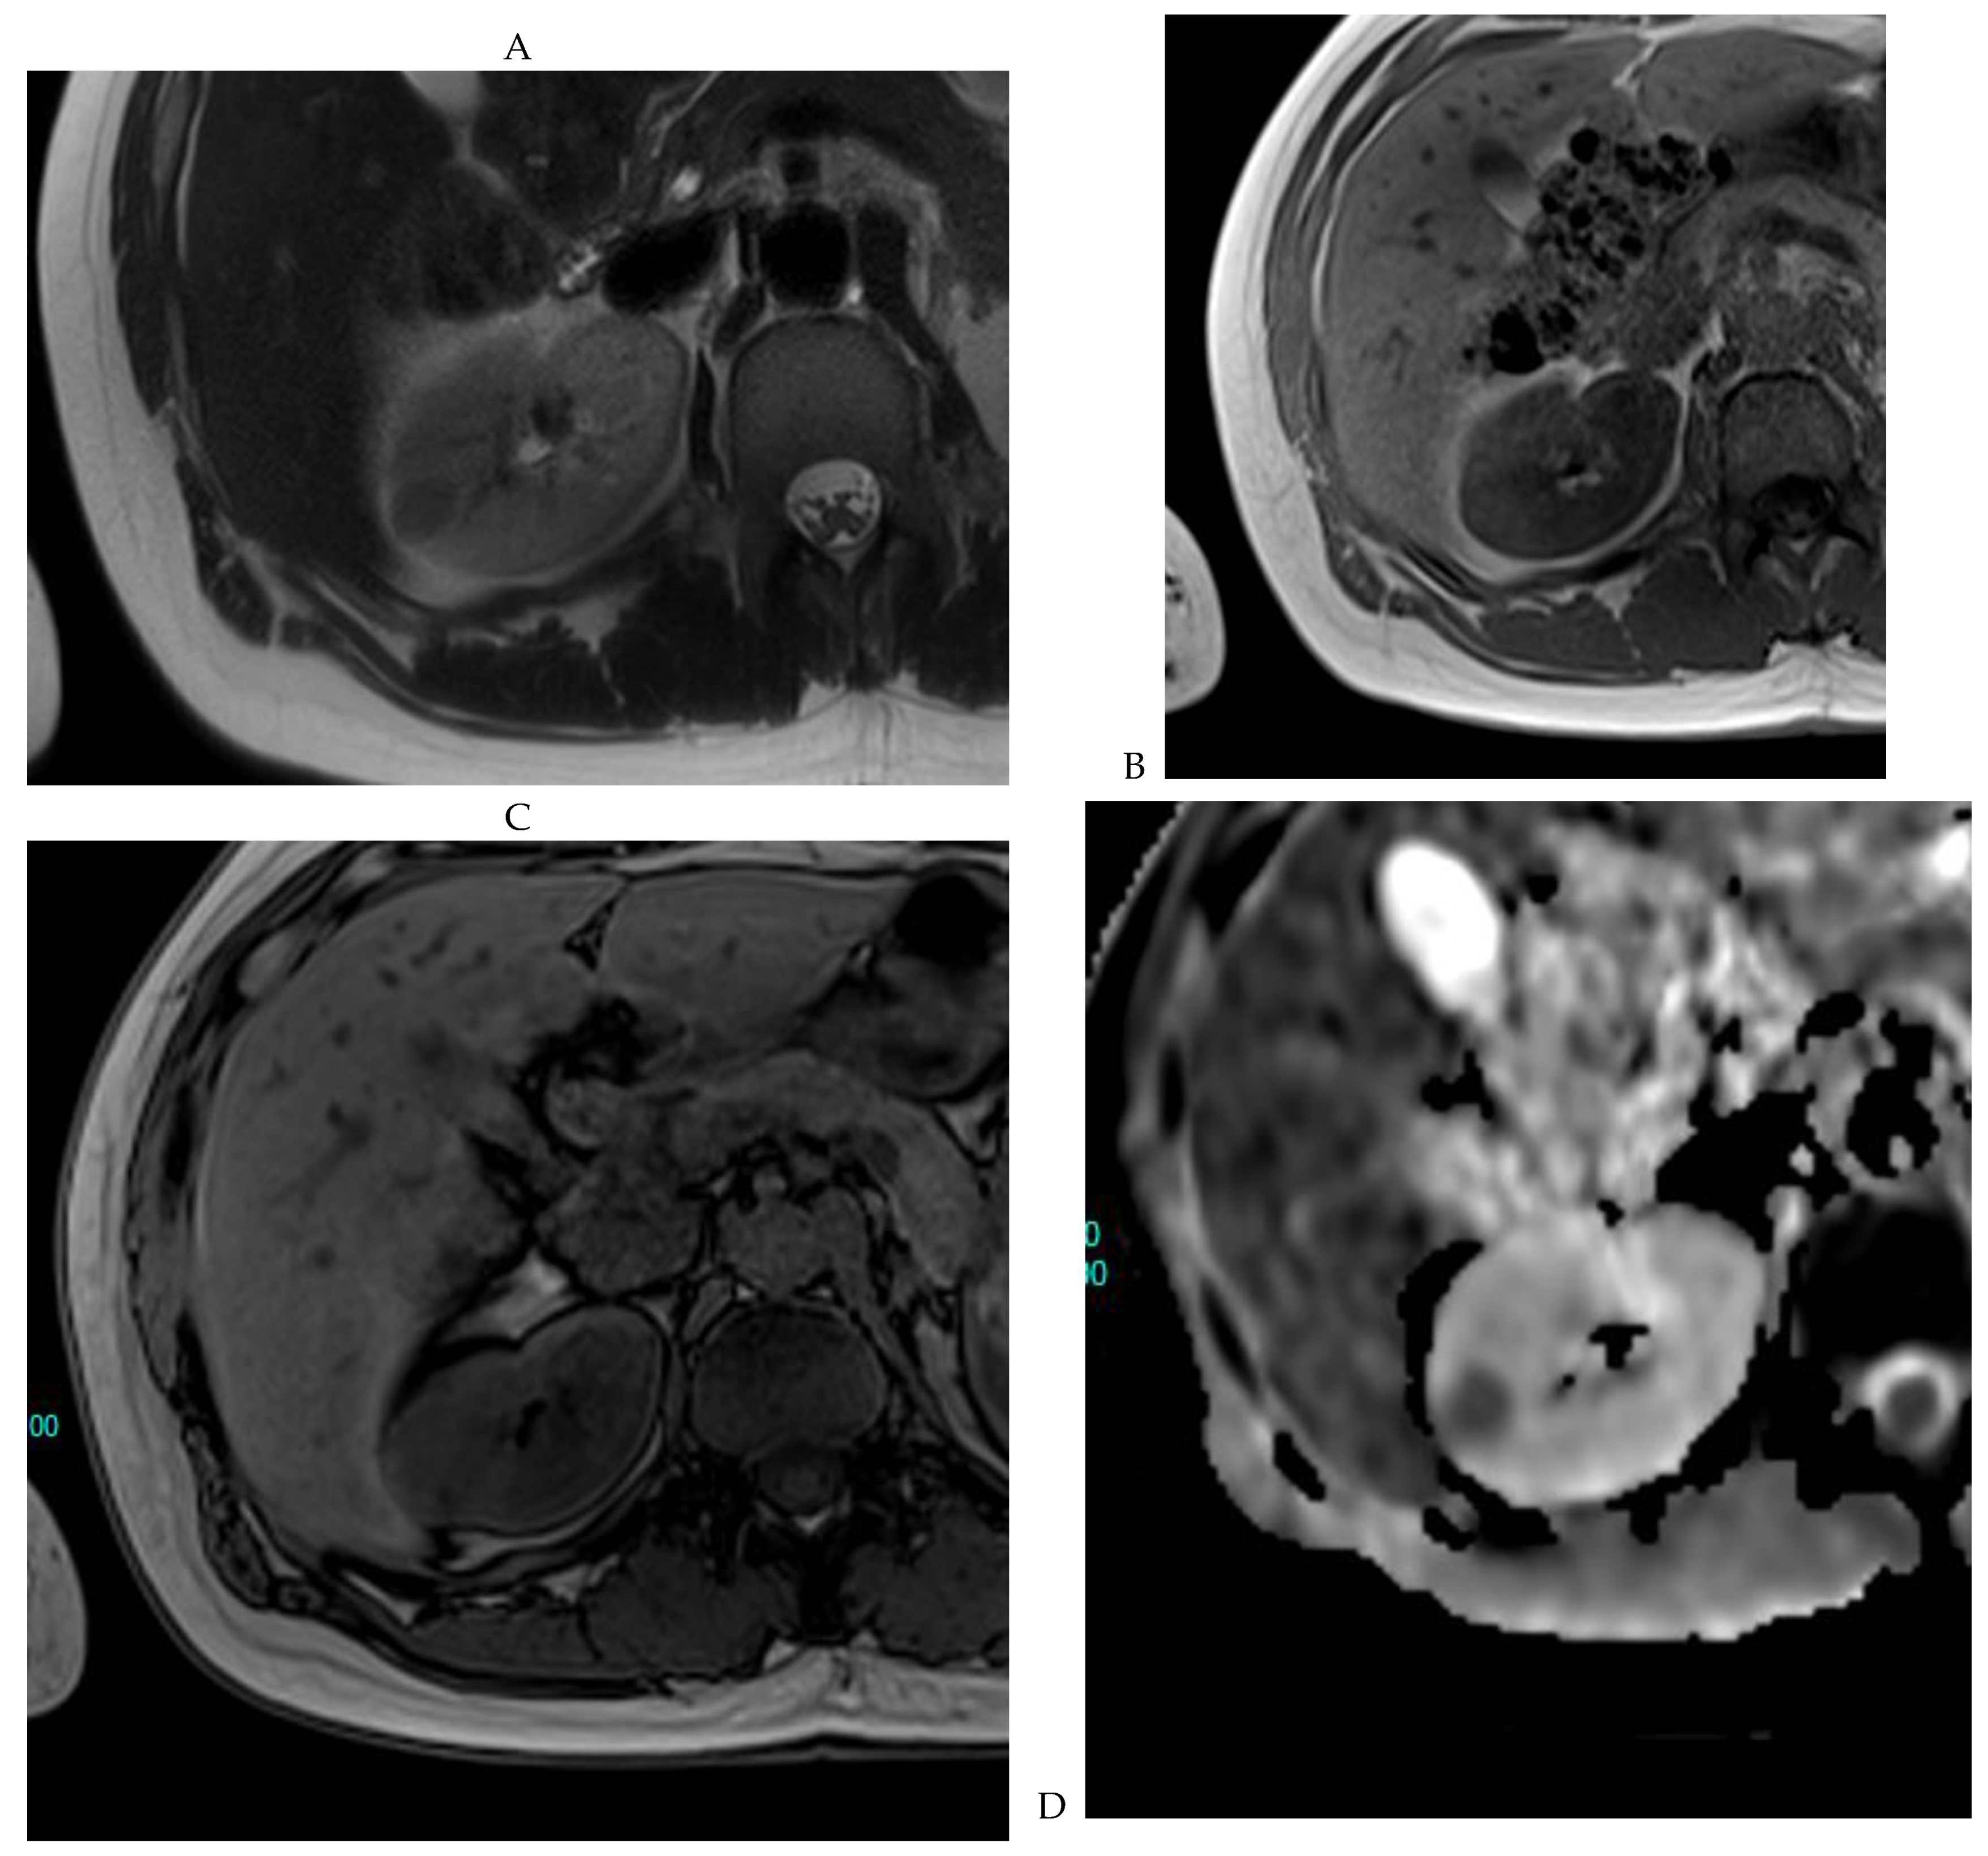

Figure 8.

Same lesion as Figure 3. Chromophobe renal cell carcinoma in the left kidney of a 68-year-old-woman. (A) Axial T2-weighted fast SE image shows the exophytic heterogeneous isointense renal mass with a posterior hyperintense area. Transverse in-phase (B,C) opposed-phase MR images show no significant loss of signal intensity on the opposed-phase image. (D) The ADC map shows restriction of tumor diffusion into the renal mass. Transverse nonenhanced (E) and gadolinium-enhanced T1-weighted gradient-echo spoiled MR images in (F) corticomedullary, (G) nephrographic, (H) and delayed phase images show a mid-intense enhancement of the lesion without visible washout.